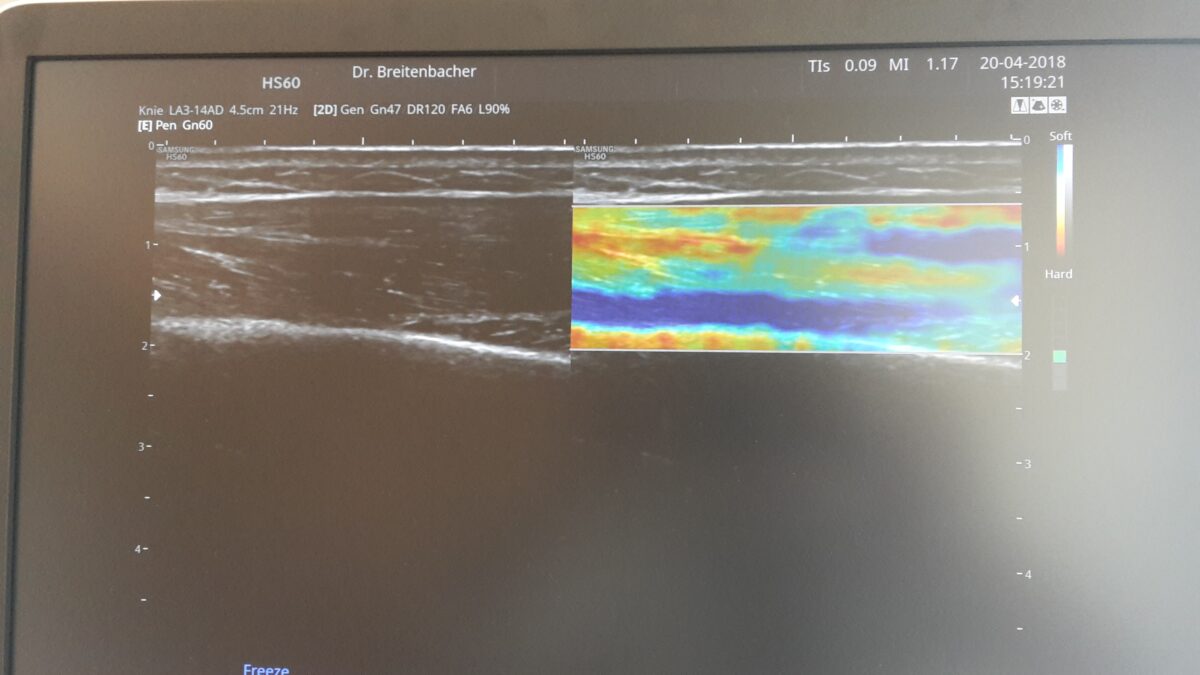

Elastographie

Nach erfolgreicher Testphase setzen wir in unserer Praxis seit einigen Monaten ein neuartiges hochauflösendes Ultraschallsystem ein mit dem wir nun in der Lage sind auch feinste Weichteilverletzungen z.B am Meniskus oder an der Schulter/Rotatorenmanschette darzustellen. Als weitere Besonderheit ist zu nennen dass wir mit der Elastographie erstmals die Möglichkeit haben verhärtete Muskel oder Faszienstränge präzise farblich darzustellen und den Therapieerfolg nach Behandlungsende dokumentieren zu können